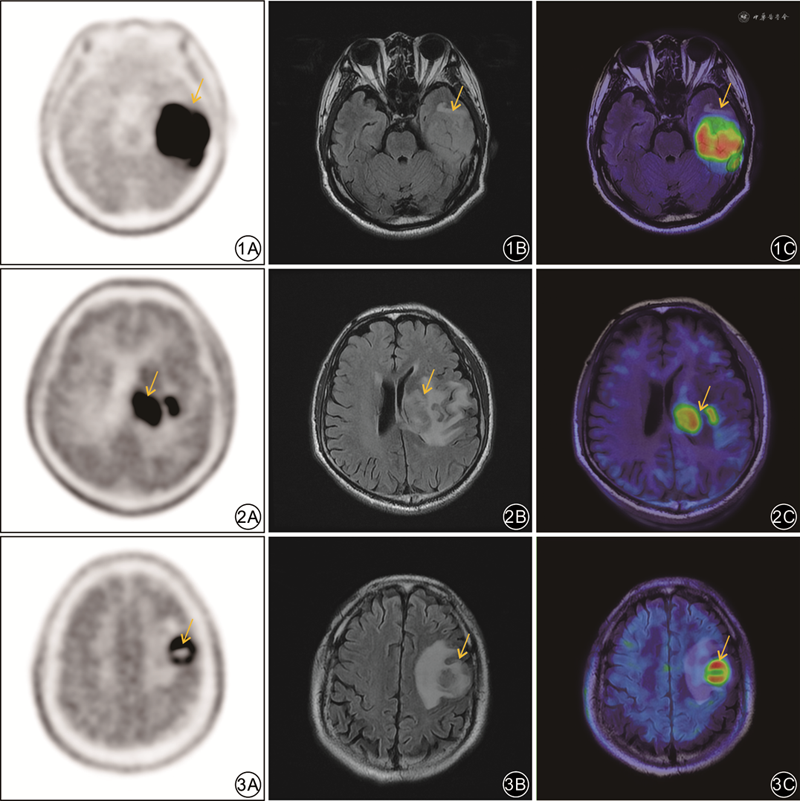

本研究结果显示,11C-MET PET/MRI对原发性胶质瘤初诊的灵敏度(91.7%)较MRI(66.7%)明显提高。初诊组MRI诊断8例假阴性,其中6例将脑胶质瘤误诊为良性病变,11C-MET PET/CT诊断4例假阴性,均将脑胶质瘤误诊为其他病理类型的恶性肿瘤。11C-MET PET/CT诊断脑胶质瘤的假阴性率(16.7%)低于MRI(33.3%),说明MRI可能对病变良恶性的鉴别诊断缺乏特异性;而11C-MET PET/CT在良恶性鉴别方面具有一定优势。然而在某些情况下,11C-MET PET对脑良恶性病变的鉴别也会有困难,主要是由于各种原因造成的血-脑屏障破坏、胶质增生、炎性细胞浸润等,可能会引起良性病变中11C-MET摄取的增加[9],但本研究中未发现类似情况。同时,我们进一步分析了PET/MRI半定量指标在病变良恶性鉴别方面的应用价值,结果发现,除了PET半定量指标SUVmax与T/N具有很大优势之外,ASL半定量指标CBF及MRS半定量指标Cho/NAA在初诊组良恶性肿瘤患者之间的差异也有统计学意义,与以往报道相同[10],说明功能MRI技术对肿瘤良恶性鉴别也具有重要价值。CBF可定量评估脑肿瘤血流灌注情况,在脑肿瘤诊断方面具有一定优势。由于肿瘤异质性,为了满足其异常增生细胞的氧供,血管内皮生长因子表达增加,进而新生血管增多,血流量丰富[11]。但ASL对运动非常敏感,易出现大量伪影[12],临床应用价值有限。MRS也存在一定的局限性:包括要求磁场均匀度足够高以保证其谱线质量,要求成像组织或区域内含脂与含水相对较少,成像体素内尽量避免包含骨板、气窦、血流、脑脊液、金属、坏死、钙化、脂肪、出血等有磁敏感效应的组织结构等[13]。以上因素均可影响分析结果的准确性,导致误诊。本研究中的图1病例是弥漫性脑胶质瘤患者,采用MRS分析其病灶的Cho峰升高、NAA峰稍降低,Cho/NAA比值较对侧轻度增加,考虑为炎性细胞浸润导致的Cho峰升高,因而被误诊为脑炎。

本研究结果还显示,11C-MET PET/CT对脑胶质瘤初诊患者的假阳性率较高,说明11C-MET PET/CT在不同病理类型恶性肿瘤的鉴别诊断中存在困难。初诊组41例中,11C-MET PET/CT诊断假阳性6例(14.6%),其中3例转移瘤与3例淋巴瘤被误诊为脑胶质瘤;在融合MRI后,其中5例(5/6)假阳性得到了纠正,因此11C-MET PET/MRI的准确性明显提高,为92.7%(38/41),高于11C-MET PET/CT或MRI,说明MRI可为11C-MET PET/CT诊断胶质瘤初诊带来明显的增益。通过进一步分析PET/MRI的不同影像特征对不同病理类型恶性肿瘤的鉴别诊断价值,发现MRI所提供的瘤周水肿、占位效应与强化特征在不同病理类型恶性肿瘤间差异有统计学意义(P<0.05),可见MRI在不同病理类型恶性肿瘤的鉴别诊断中为11C-MET PET提供重要增益价值。

本研究中,对24例临床怀疑残留/复发性胶质瘤的患者研究结果表明:11C-MET PET在鉴别肿瘤残留/复发与治疗后改变时,其灵敏度与准确度均优于MRI,与以往报道相同[14]。肿瘤细胞处于异常增殖状态,尤其是脑胶质瘤残留/复发时,其恶性程度可进一步增加,氨基酸代谢率也大幅提高,导致11C-MET在病变部位明显富集[15];而由于手术或放疗等治疗手段可能会导致血-脑屏障的损伤、胶质增生与炎性细胞浸润,有时会引起治疗后11C-MET摄取增加,增加的幅度一般会低于肿瘤残留/复发[16],但二者之间的SUVmax值仍会存在一定的重叠。Tripathi等[17]研究表明,肿瘤与正常脑组织的SUVmax比值(T/N)>1.9是11C-MET PET/CT区分残留/复发性脑胶质瘤与治疗后改变的最佳截断值,灵敏度与特异度可达95%与89%;Deuschl等[18]以T/N1.47作为最佳截断值,灵敏度与特异度分别为76%与87%。D'Souza等[19]对11C-MET PET/CT与MRI对脑胶质瘤治疗后是否残留/复发的评估效能进行比较,结果显示11C-MET PET/CT在识别肿瘤复发/残留方面表现出更高的灵敏度(94.7%),MRI则表现出更高的特异度(90.0%)。在本研究中,11C-MET PET/CT对残留/复发性胶质瘤诊断灵敏度(86.7%)高于MRI(66.7%),MRI的特异度(77.8%)高于11C-MET PET/CT(66.7%)。因此,两者融合可在一定程度上优势互补,大大提高诊断性能(95.8%),与既往研究结果相仿(96.0%)[18]。